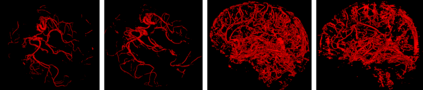

The use of deep learning techniques for 3D brain vessel image segmentation has not been as widespread as for the segmentation of other organs and tissues. This can be explained by two factors. First, deep learning techniques tend to show poor performances at the segmentation of relatively small objects compared to the size of the full image. Second, due to the complexity of vascular trees and the small size of vessels, it is challenging to obtain the amount of annotated training data typically needed by deep learning methods. To address these problems, we propose a novel annotation-efficient deep learning vessel segmentation framework. The framework avoids pixel-wise annotations, only requiring patch-level labels to discriminate between vessel and non-vessel 2D patches in the training set, in a setup similar to the CAPTCHAs used to differentiate humans from bots in web applications. The user-provided annotations are used for two tasks: 1) to automatically generate pixel-wise labels for vessels and background in each patch, which are used to train a segmentation network, and 2) to train a classifier network. The classifier network allows to generate additional weak patch labels, further reducing the annotation burden, and it acts as a noise filter for poor quality images. We use this framework for the segmentation of the cerebrovascular tree in Time-of-Flight angiography (TOF) and Susceptibility-Weighted Images (SWI). The results show that the framework achieves state-of-the-art accuracy, while reducing the annotation time by up to 80% with respect to learning-based segmentation methods using pixel-wise labels for training